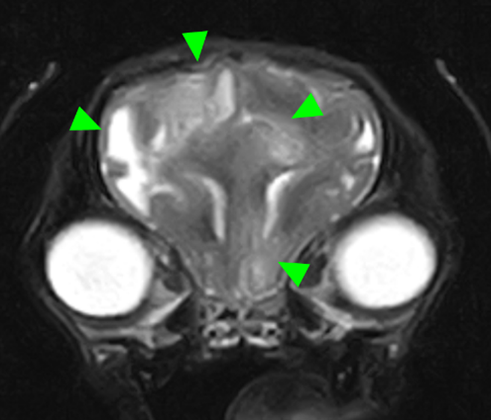

本症例のMRI検査所見:

・前頭葉白質領域(右>左)および右側大脳白質領域(側頭葉・後頭葉)にT2強調画像/FLAIR画像で高信号を示し、一部造影増強を示すびまん性の所見を認める。この所見は、DWI画像で高信号を示し、ADC-mapで大半は等~低信号を示す。

・透明中隔は欠損を疑うが、顕著な側脳室拡大を疑う所見は認められず、脳溝も明瞭である。